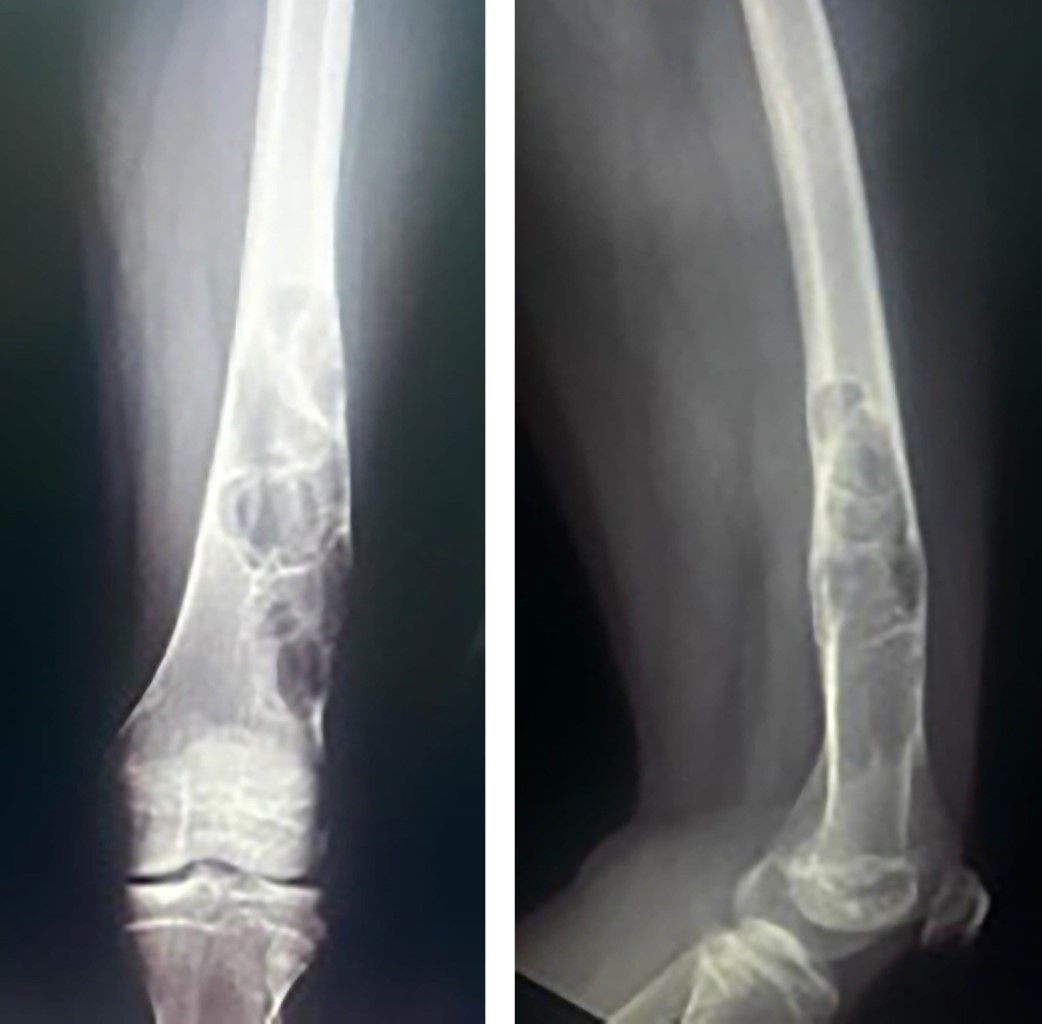

Paciente adolescente femenina de 12 años es evaluada en compañía de su madre, derivada por gonalgia izquierda en estudio de un año de evolución y tumor de fémur distal y tibia proximal izquierda, que se evidencia en radiografía anteroposterior (AP) y lateral de rodilla izquierda (Figura 1) y en radiografía AP y lateral de fémur distal izquierdo (Figura 2). Al examen físico presenta claudicación a la marcha y rango de movilidad de rodilla izquierda disminuido con dolor a la flexión > 90°. Se realizó resonancia magnética nuclear con contraste (Figura 3) con el hallazgo de una lesión hipercaptante, hipointensa en T1, hiperintensa en T2, además de lesión cortical a nivel de ambos fémures distales. Se complementa estudios con exámenes endocrinos con resultados dentro de límites normales y radiografías de huesos largos descartando algún otro foco de lesión.

Figura 1